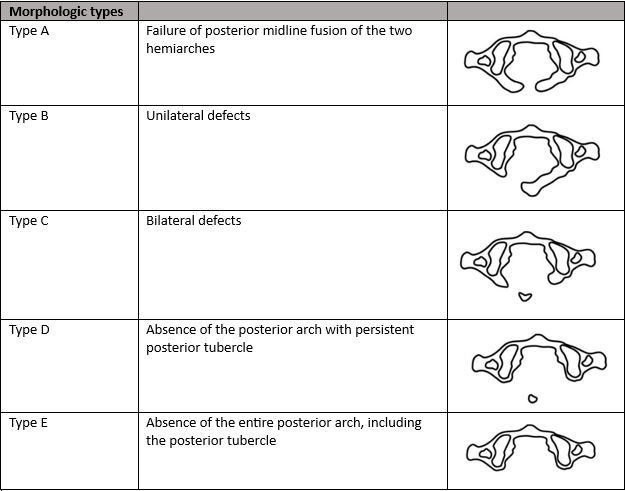

Hypoplasia of the posterior arch of the atlas is an uncommon congenital anomaly that is seen in up to 4% of the population.1. These anomalies are often considered simply benign congenital anomalies without clinical significance; however, this assumption is not always the case. The degree of posterior arch hypoplasia may range from a thin posterior midline defect, due failure of midline fusion of the two hemiarches, to complete aplasia of the posterior arch. Clinicians often find these defects incidentally on cervical spine radiographs but may be unsure of how to proceed after discovering the anomaly. This article will focus on understanding the different morphologic types of hypoplasia of the posterior arch of the atlas, as well as clinical considerations based on radiographic and clinical findings.

The most commonly used classification system is the Currarino classification, which describes both morphological types and clinical subgroups.2

Isolated hypoplasia of the posterior arch of the atlas variations are generally considered benign anomalies and are generally asymptomatic; however, neurologic symptoms, ranging from mild neck pain to intermittent quadriparesis, have been found to occur with cervical extension or after minor cervical traumaquadriparesis.1,3 Type A and subgroup 1 are the most common and account for 80-90% of the cases.1 These cases do not seem to place the patient at neurologic risk. Type C and D are considered to potentially be problematic due to the possibility of impingement of the cord by the posterior tubercle during extension.

The transient nature of the neurologic symptoms or their appearance following minor cervical trauma appears to correlate with the anatomic observations associated with the Type C and D anomalies. It is suggested that in Types C and D (those with an isolated posterior bony fragment) that inward mobility of the posterior fragment is possible.4. Autopsy and surgical studies have shown that the gap between the osseous fragments is bridged by loose connective tissue, rather than cartilage. Therefore, it is possible that the isolated posterior tubercle can move in dissociation from the anterior arch. This is particularly important to consider during cervical extension in which cord impingement may occur due to a reduction in the distance between the occiput and the spinous process of C2, which can lead to inward buckling of the attached ligaments causing displacement of the isolated fragment anteriorly into the spinal canal.4 This compression of the cord can cause focal myelomalacia, cord edema, or a pre-syrinx state.4

When considering the appropriateness of cervical manipulation in patients with hypoplasia of the posterior arch of the atlas, it is important to consider each type separately. Please note that the term “cervical manipulation” will refer to high velocity low amplitude (HVLA) spinal manipulation and not soft tissue or low amplitude type manipulation. Neurologically stable patients with Type A or B do not appear to have the risk of cord impingement, and, therefore, manipulation would not be contraindicated. Type C and D (of any clinical subgroup) do have the risk of cord impingement during cervical extension and/or neurologic injury following minor trauma, and, therefore, in this author’s opinion, HVLA upper cervical manipulation and cervical extension-based soft tissue manipulation/ mobilization are contraindicated. Additionally, these patients should be advised to avoid contact sports, and advanced imaging studies (MRI unless contraindicated) should be performed in those patients that are neurologically symptomatic.4 Surgery is the treatment of choice in patients with instability or compression and may include posterior fusion or surgical excision of the posterior arch.